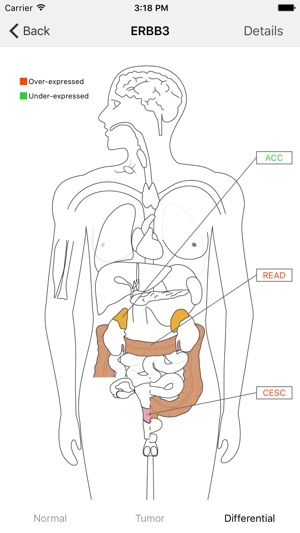

This GE-mini APP is designed to exhibit gene expression profiling of a given gene over many tissue types including tumors. The underlying data are based on RNA Sequencing results from both TCGA and GTEx after they are normalized and integrated. The current version, based on the September 2015 release of TCGA and the phs000424.v6.p1 release of GTEx, contains >19,000 total samples across 33 cancer types and 53 normal tissue types.